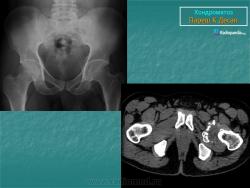

Хондроматоз

Приложения:

41.osteochondromatosis.jpg42.synovial.jpg